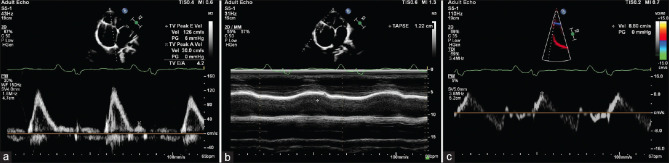

部分腔肺分流术是针对右心室(RV)生理异常患者的一种成熟手术。格伦分流术的晚期失败通常是由于原发疾病的进一步发展所致。然而,也有可能出现意外,就像我们的患者一样。我们报告了一名被诊断为三尖瓣(TV)发育不良并伴有边缘性 RV 发育不良的 8 岁儿童。他接受了 TV 修复术和右腔-肺分流术。手术 6 年后,他出现了心力衰竭的症状。超声心动图评估显示,他的左心室呈限制性充盈模式,但大小和功能均有所保留。计算机断层扫描和心脏磁共振成像显示心包厚度正常,没有心肌受累的迹象。尽管临床和影像学特征相互矛盾,但心内膜活检证实了去氨心肌病的诊断。尽管进行了广泛的影像学检查,但限制性心肌病仍可能是一种难以确诊的疾病。在我们的病例中,腔肺分流导致的负荷条件改变进一步掩盖了病理生理血流动力学变化。

Partial cavopulmonary shunt is an established procedure for patients with abnormal right ventricular (RV) physiology. Late failure of the Glenn shunt is usually due to further progression of the primary disease process. However, there may be surprises, as in our patient. We report an 8-year-old child who was diagnosed with tricuspid valve (TV) dysplasia with borderline RV hypoplasia. He underwent TV repair with a right cavopulmonary shunt. He presented with features of heart failure after 6 years of the surgery. An echocardiographic evaluation suggested a restrictive filling pattern of the RV with preserved size and function. Computed tomography and cardiac magnetic resonance imaging revealed a normal pericardial thickness with no evidence of myocardial involvement. Despite the contradicting clinical and imaging features, endomyocardial biopsy confirmed a diagnosis of desmin cardiomyopathy. Restrictive cardiomyopathy may remain an elusive diagnosis despite extensive imaging. In our case, the altered loading conditions due to a cavopulmonary shunt further masked pathophysiological hemodynamic changes.